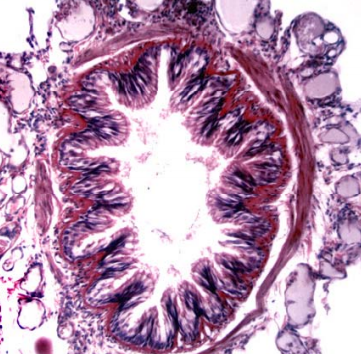

what is this slide of?

lung bronchus

regular bronchiole

folding

no visible cartilage

smooth muscle